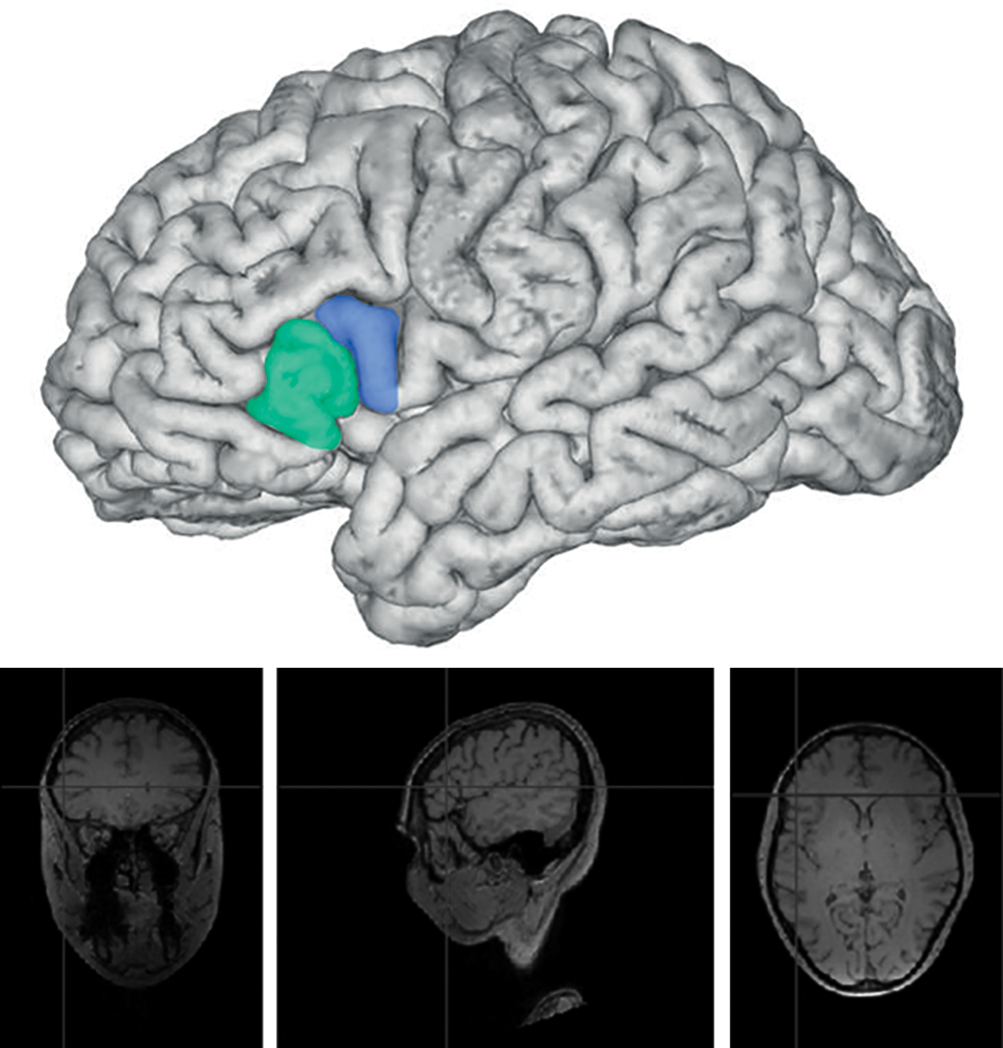

Установлены принципиальные изменения строения мозга мужчин-музыкантов в сравнении с мозгом мужчин контрольной группы и мозга женщин-музыкантов в сравнении с мозгом женщин контрольной группы. При сравнительном анализе макроскопического строения зоны Брока левого полушария (ЛП) мозга у женщин-музыкантов установлено более сложное строение триангулярной области коры мозга мозга, чем у женщин контрольной группы. В мозге женщин-музыкантов в сравнении с мозгом женщин контрольной группы отмечается наличие дополнительных бороздок, особенно в триангулярной области, и слияние триангулярной области с оперкулярной областью и орбитальной областью мозга за счёт наличия межуточных формаций, увеличивающих размеры как триангулярной, так и оперкулярной области (рис. 1, 2).

Рис. 2. Строение зоны Брока мозга женщины контрольной группы, ЛП. Зелёным цветом обозначена триангулярная область, синим цветом — оперкулярная.

Fig. 2. Structure of Broca’s area in the brain of a female non-musician, LH. Triangular region is shown in green; opercular region is shown in blue.